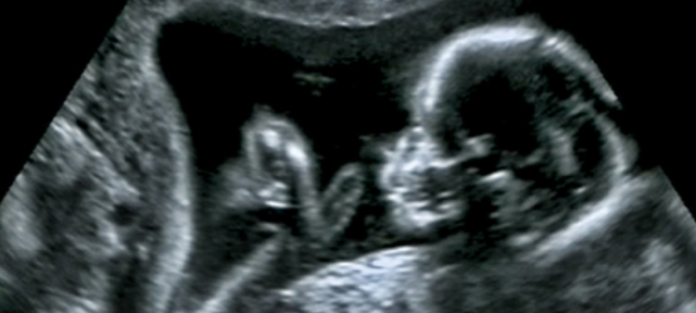

Now, a new study published in The Journal of Immunology has found a link between the gut microbiome and the neurodevelopmental condition autism using animal studies. However, it is not our own microbiome that affects whether or not we develop autism, the researchers say – it’s our mom’s.

When the IL-17a molecule was artificially blocked (preventing IL-17a-induced inflammatory responses), the pups from both sets of mice were born with neuro-typical behaviors. Yet, when everything was left to progress without additional human intervention, the pups born from mothers in the first group went on to develop an autism-like neurodevelopmental condition, which affected social and repetitive behaviors.

To confirm that this was due to the group’s unique microflora, the researchers performed a fecal transplant on mice from the second group using the feces of the mice from the first group. The idea here is to change the microflora of the second group so that it more closely resembles that of the first. And, as expected, the pups from the second group went on to develop an autism-like neurodevelopmental condition.

These are preliminary studies and may not translate to human pregnancies, but it does offer an interesting avenue to explore as far as autism research is concerned and provides strong evidence that the health of the mother’s gut plays at least some role in the onset of neurodevelopmental conditions.